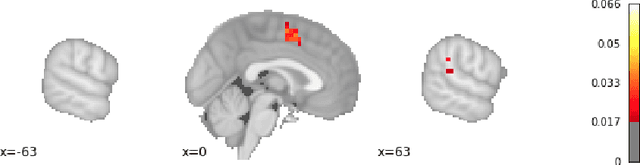

Abstract:Researchers in neuroscience have a growing number of datasets available to study the brain, which is made possible by recent technological advances. Given the extent to which the brain has been studied, there is also available ontological knowledge encoding the current state of the art regarding its different areas, activation patterns, key words associated with studies, etc. Furthermore, there is an inherent uncertainty associated with brain scans arising from the mapping between voxels -- 3D pixels -- and actual points in different individual brains. Unfortunately, there is currently no unifying framework for accessing such collections of rich heterogeneous data under uncertainty, making it necessary for researchers to rely on ad hoc tools. In particular, one major weakness of current tools that attempt to address this kind of task is that only very limited propositional query languages have been developed. In this paper, we present NeuroLang, an ontology language with existential rules, probabilistic uncertainty, and built-in mechanisms to guarantee tractable query answering over very large datasets. After presenting the language and its general query answering architecture, we discuss real-world use cases showing how NeuroLang can be applied to practical scenarios for which current tools are inadequate.